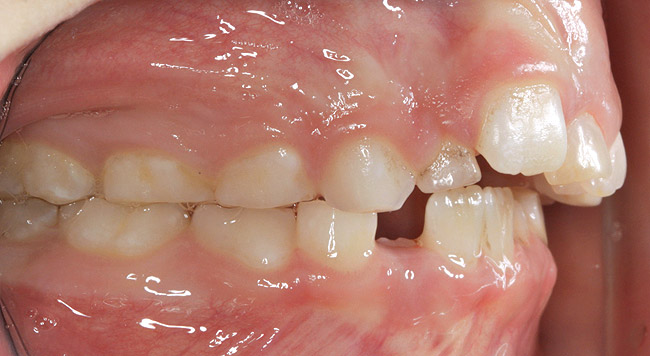

(3.) Three-year-old with a history of snoring, bruxing, and thumbsucking. Her father and brother were both diagnosed with OSA.

Figure 3

(4.) Patient presents bilateral crossbite and significant attrition. Father assists in retraction.

Figure 4

The pattern for bone growth resides not in the bone itself but rather in the soft tissue and muscle that encase the bone.42 Oral-facial muscle tone and tongue tonicity create a framework for normal development of the nasomaxillary complex and mandible.43 SDB is noted in children with pathologic hypotonia of facial and tongue muscles. Children born with a normal palate and oral-facial hypotonia will develop a high, narrow palate over the first year of life (Figure 3 and Figure 4). Children born with a high, narrow palate have hypotonia at birth. These myofunctional changes may be detected in utero.43